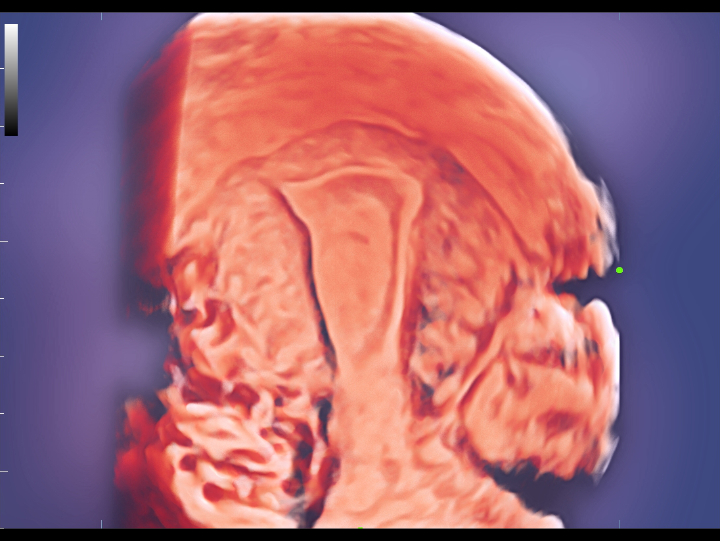

Pelvic ultrasound is considered as the first choice of imaging examination method to evaluate suspected gynecological diseases in women of all ages. Ultrasonography is usually the only necessary imaging examination to diagnose uterine, ovarian and adnexal diseases because of its wide availability, low cost and advantages of no ionizing radiation. With the development of volume ultrasound technology, 3D ultrasound has become a routine gynecological examination item. Through the acquisition of volume data, 3D ultrasound can display the uterus, cervix, ovary and uterine adnexa on any plane, and has more advantages in evaluating the uterine cavity.

UWN+ CEUS provides excellence contrast agent sensitivity and image penetration to get more diagnosis information for gynecology tumor or other difficult diseases. Also MindrayŌĆÖs STE (Sound Trouch Elastogtaphy) can quantitatively evaluate tissue stiffness which is helpful for previse diagnosis of difficult uterus, cervix and ovary diseases.